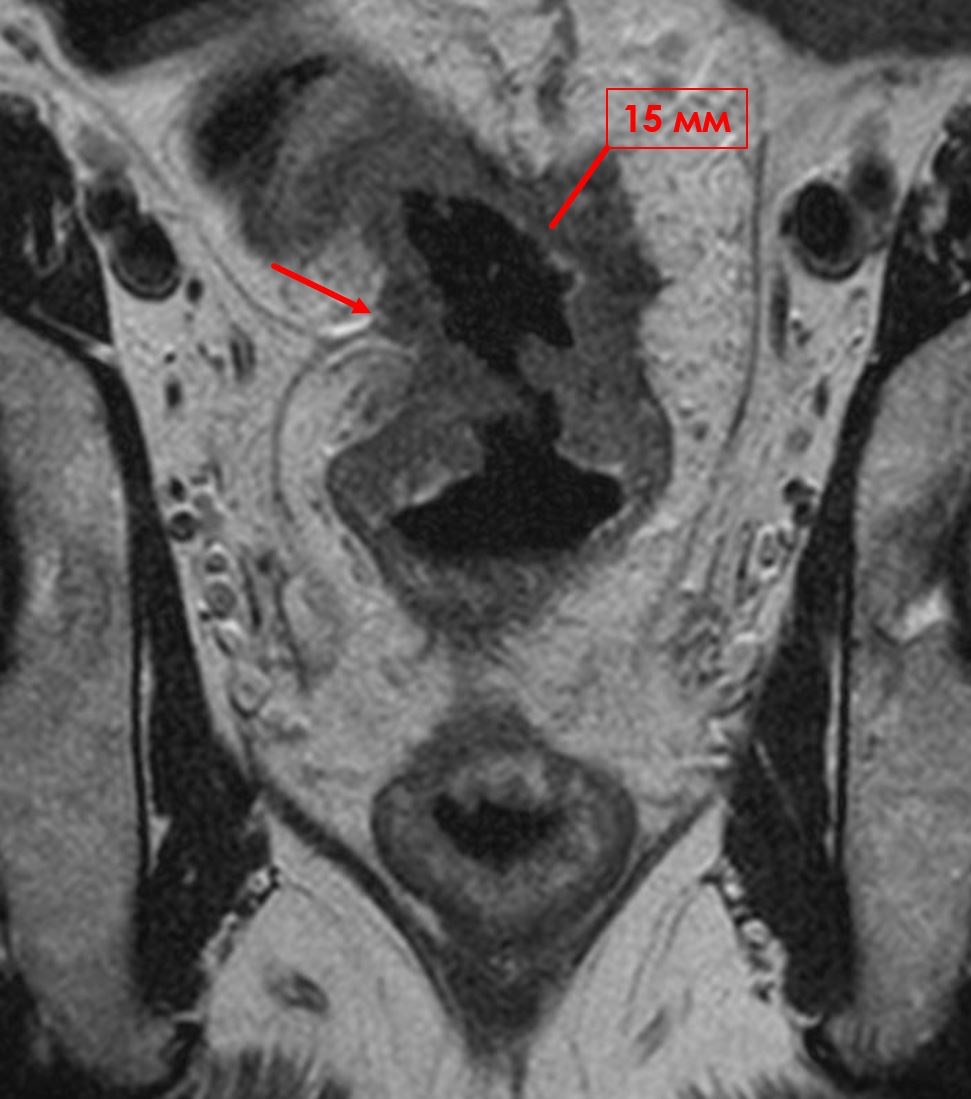

955. На мр-томограмме в верхнеампулярном отделе прямой кишки выявляется циркулярная опухоль, инфильтрирующая все слои кишечной стенки, клетчатку на глубину до 15 мм и тазовую брюшину на уровне переходной складки, что соответствует глубине инвазии